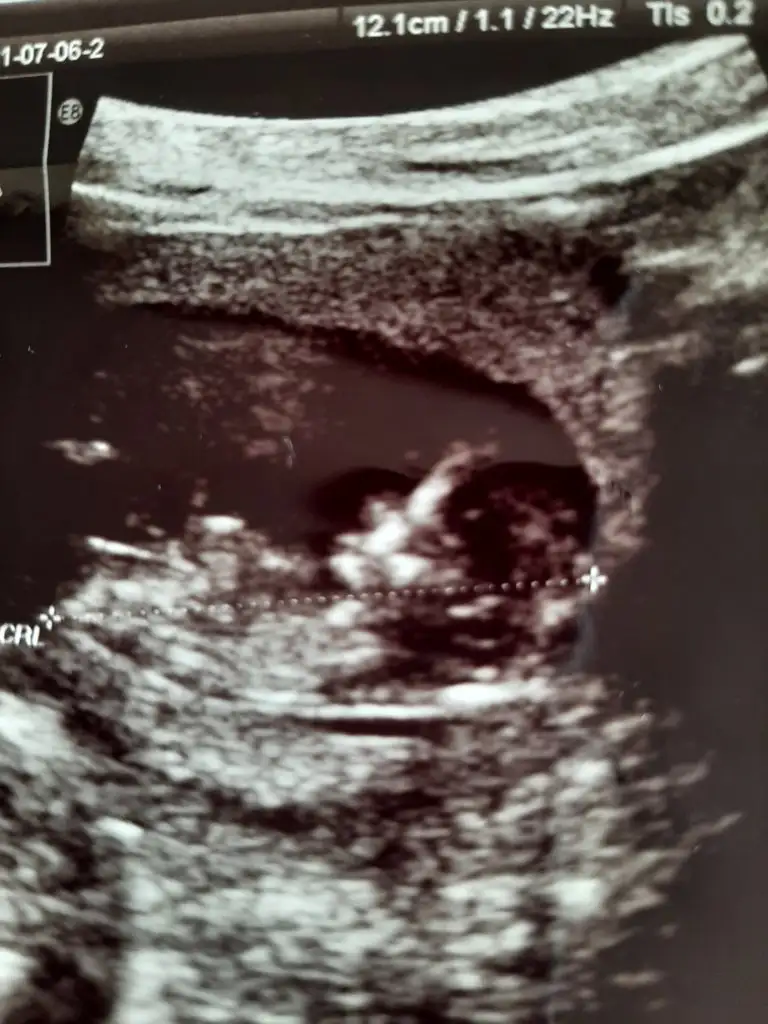

• 16255793867346262906064342910674.webp

16255793867346262906064342910674.webp

36,6 KB · Görüntüleme: 46